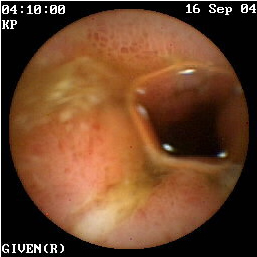

Η κάψουλα έχει επίσης ιδιαίτερη αξία στην ανεύρεση της εστίας της αιμορραγίας αγνώστου αιτιολογίας στη νόσο του Crohn (εικόνες 1,2). Οι Legnaniκαι συν του16 εκτίμησαν 11 ασθενείς με νόσο Crohnκαι αδιευκρίνιστη αιμορραγία και προσδιόρισαν την ακριβή αιτία της στους 9 από αυτούς.

1  2

Eικόνα 1. Βαριά φλεγμονή του βλεννογόνου             Εικόνα 2. Αυτόματη αιμορραγία ειλεού σε ασθενή

με σχηματισμό ψευδοπολύποδα.                             με γνωστή νόσο Crohn